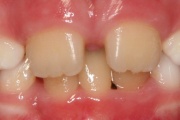

Turritavad ülemised lõikehambad.

Ülemise hambakaare kitsenemine ehk tagumiste hammaste risthambumus.